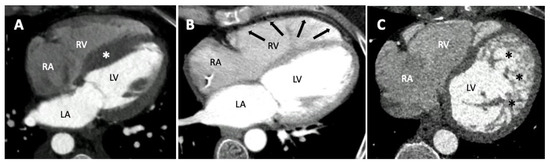

4.2. Role of CT in Paediatric Cardiomyopathies

- Ko, S.M.; Hwang, S.H.; Lee, H.J. Role of Cardiac Computed Tomography in the Diagnosis of Left Ventricular Myocardial Diseases. J. Cardiovasc. Imaging 2019, 27, 73–92. [Google Scholar] [CrossRef]

- Clayton, B.; Roobottom, C.; Morgan-Hughes, G. Assessment of the myocardium with cardiac computed tomography. Eur. Heart J. Cardiovasc. Imaging 2014, 15, 603–609. [Google Scholar] [CrossRef]

- Conte, E.; Mushtaq, S.; Muscogiuri, G.; Formenti, A.; Annoni, A.; Mancini, E.; Ricci, F.; Melotti, E.; Gigante, C.; Lorenza, Z.; et al. The Potential Role of Cardiac CT in the Evaluation of Patients with Known or Suspected Cardiomyopathy: From Traditional Indications to Novel Clinical Applications. Front. Cardiovasc. Med. 2021, 8, 709124. [Google Scholar] [CrossRef]

- Williams, T.J.; Manghat, N.E.; McKay-Ferguson, A.; Ring, N.J.; Morgan-Hughes, G.J.; Roobottom, C.A. Cardiomyopathy: Appearances on ECG-gated 64-detector row computed tomography. Clin. Radiol. 2008, 63, 464–474. [Google Scholar] [CrossRef] [PubMed]

- Zenooz, N.A.; Zahka, K.G.; Siwik, E.S.; Gilkeson, R.C. Noncompaction Syndrome of the Myocardium. J. Thorac. Imaging 2010, 25, 326–332. [Google Scholar] [CrossRef] [PubMed]